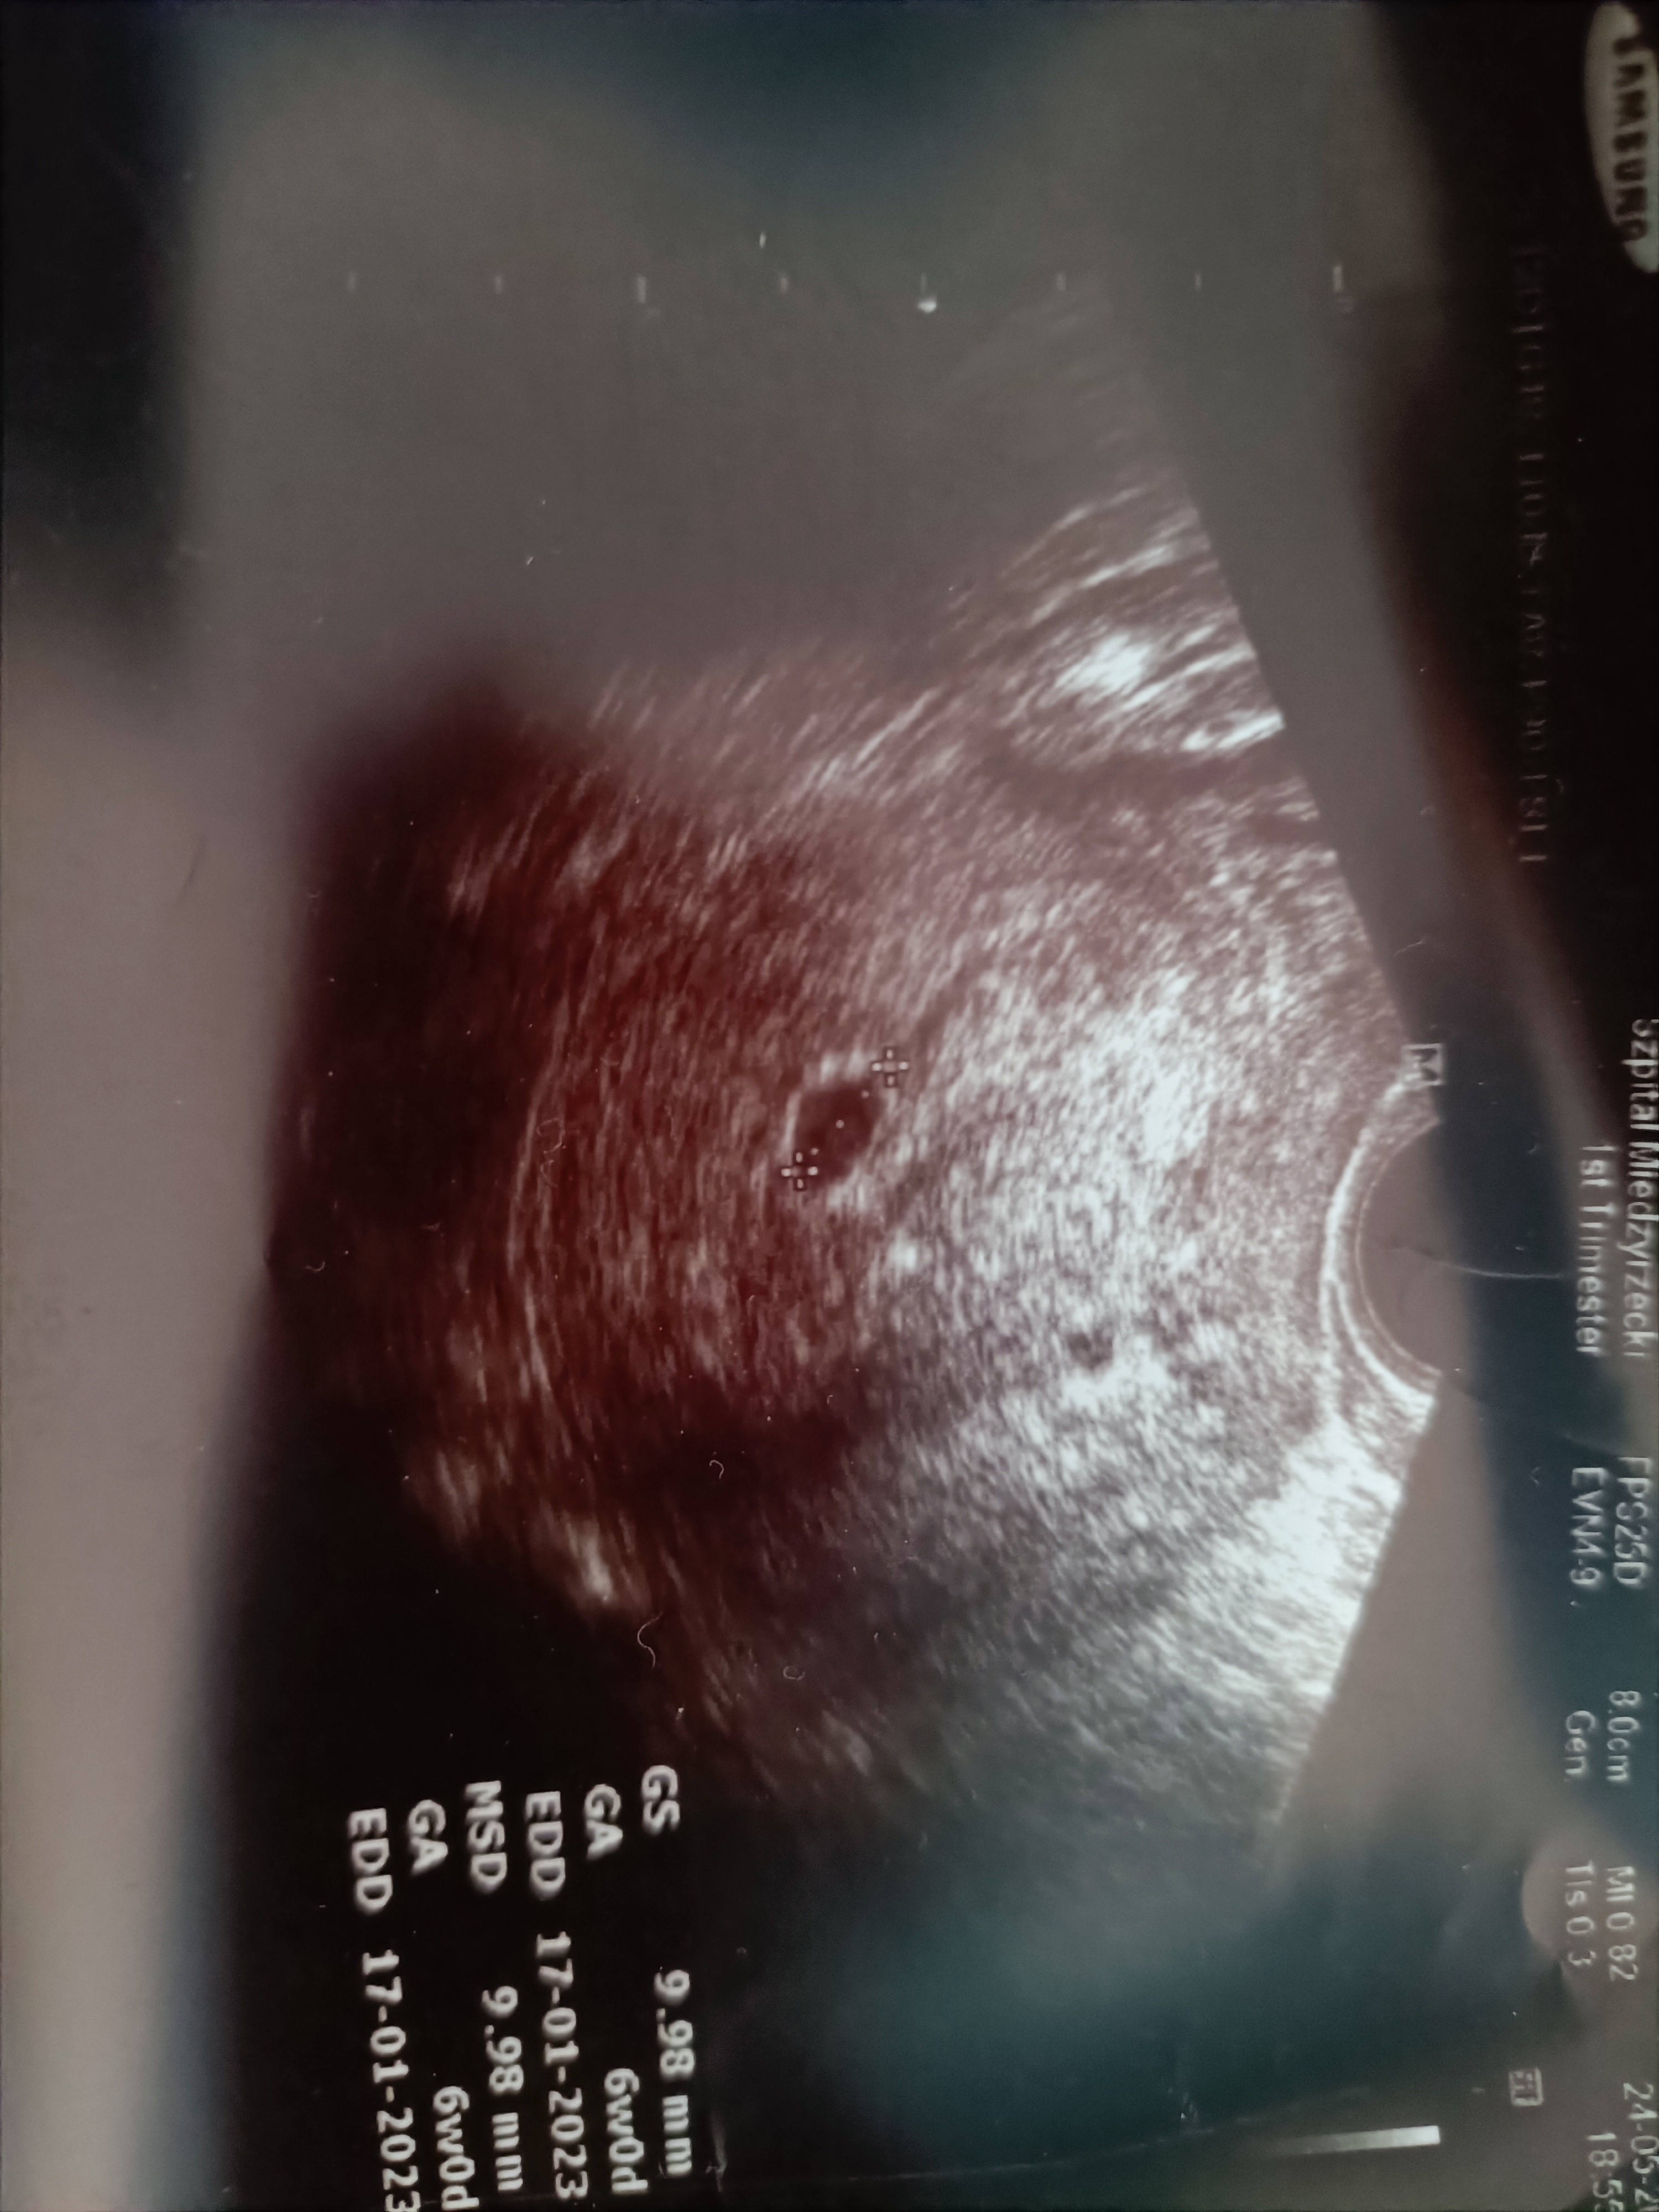

Załączniki

• IMG20220525114430.jpg

IMG20220525114430.jpg

1,7 MB · Wyświetleń: 112